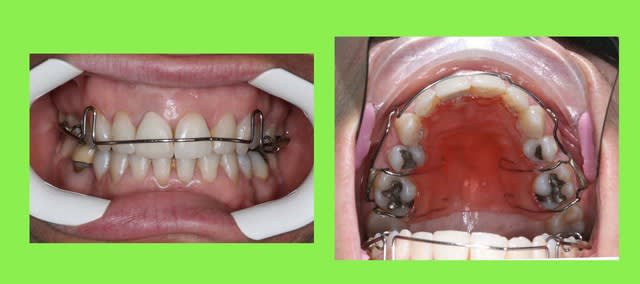

ça c'est de la contention.

je vais démonter cette contention et essayer de faire un peu mieux que ça.

quelle est la meilleure méthode pour faire une contention au maxillaire, sachant que les latérales vont sûrement avoir des facettes ou des couronnes.

-fil de fer?

-ribbond?

-autre?